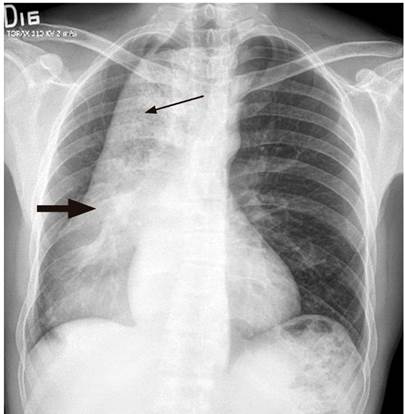

A 42-year-old male driver, with no relevant medical history, consulted due to 3 years of progressive dysphagia initially for solids and then for liquids, and regurgitation, with a worsening of symptoms in the last 4 months associated with a weight loss of 15 kg (Eckardt score 9). On admission, the patient showed signs of severe malnutrition and halitosis, without dyspnea, peripheral lymphadenopathy, visceromegaly, or ascites. A nasogastric intubation was carried out, obtaining abundant food drainage. A chest x-ray was performed in which an apparent mediastinal mass displacing the midline was observed (Figure 1). In view of this finding and persistent dry cough, an enhanced chest computed tomography (CT) scan was performed, in which megaesophagus and suggestive findings of achalasia were reported, but no neoplastic involvement of the gastroesophageal junction could be ruled out (Figure 2).

Figure 1 Chest x-ray, posteroanterior (PA) view. Mediastinal mass extending to the right and posterior to the mediastinum (thick arrow). Irregular air-fluid level and heterogeneous opacity content suggestive of food (thin arrow). Source: Gastroenterology Unit. Hospital Universitario San Ignacio. Bogotá D.C. Colombia.